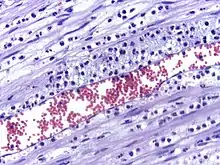

La perméabilité accrue des vaisseaux sanguins entraîne une exsudation (fuite) de liquide dans les tissus. La fuite de liquide provoque une augmentation de la viscosité du sang, ce qui augmente la concentration des globules rouges (congestion veineuse).

Les leucocytes engloutissent les microbes et les détruisent, générant la production de pus. Le pus sera éliminé vers l'extérieur si la lésion est en contact avec l'extérieur, ou il générera un abcès si la zone où s'est formé le pus est à l'intérieur d'un organe.